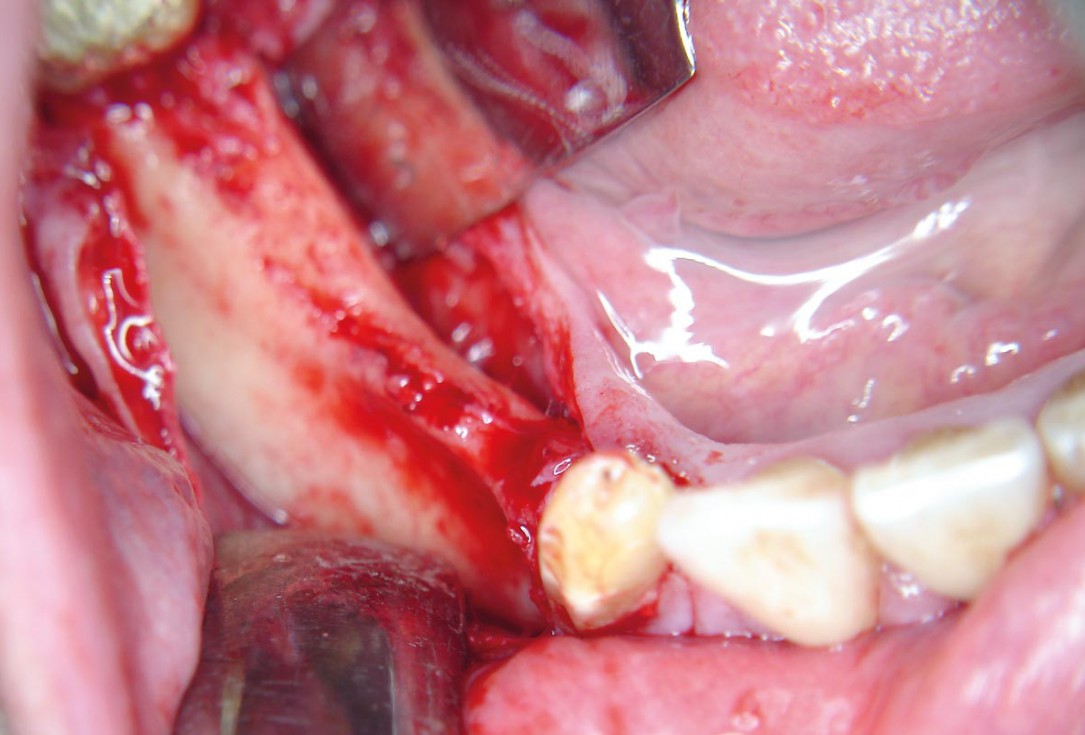

02 / 20 - Thin soft tissue and reduced mandibular widthHorizontal ridge augmentation with maxgraft® cortico - M.Sc. E. Kapogianni

03 / 20 - Flap projection shows pronounced bone lossHorizontal ridge augmentation with maxgraft® cortico - M.Sc. E. Kapogianni